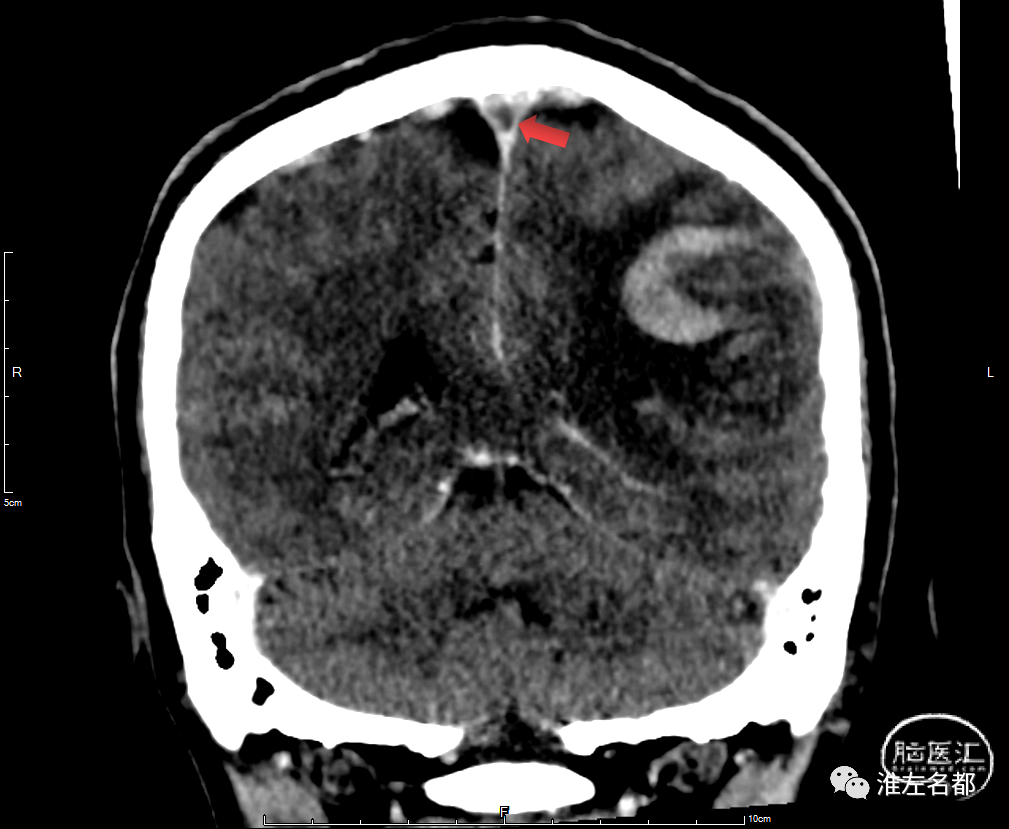

术前CT平扫:左侧颞顶叶出血性梗死,水肿占位效应明显。

术前增强CT冠状面重建:可见上矢状窦内血栓充盈缺损(红箭)。

术前CT平扫:双侧半球弥漫肿胀,脑沟脑池受压显示不清;双侧侧脑室显影狭小。